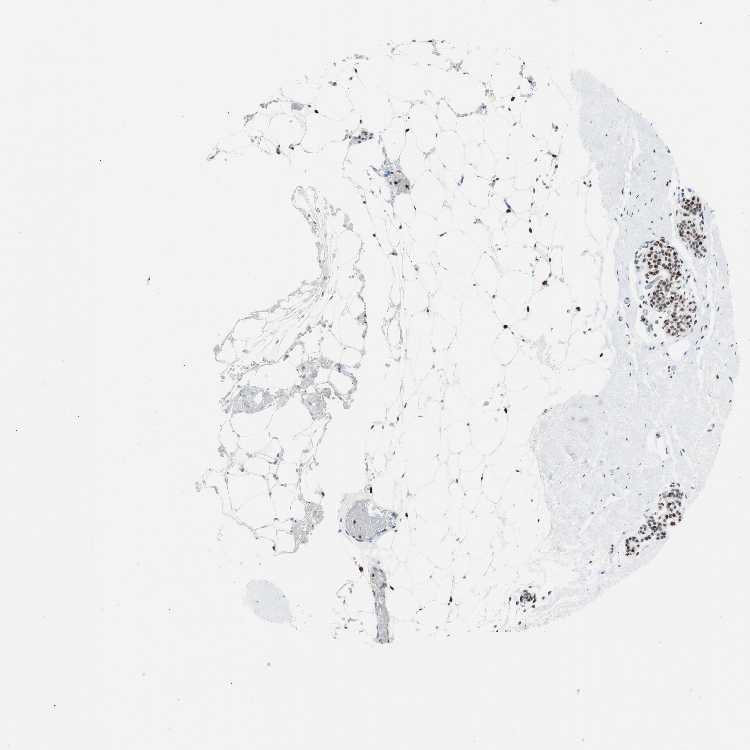

BREAST - Antibody stainingi

Antibody staining in the annotated cell types in the current human tissue is reported as not detected, low, medium, or high, based on conventional immunohistochemistry profiling in selected tissues. This score is based on the combination of the staining intensity and fraction of stained cells.

Each image is clickable and will lead to virtual microscopy that enables deeper exploration of all samples and also displays staining intensity scores, fraction scores and subcellular localization as well as patient and tissue information for each sample.

Antibody CAB004213

Adipocytes Medium

Glandular cells High

Myoepithelial cells High